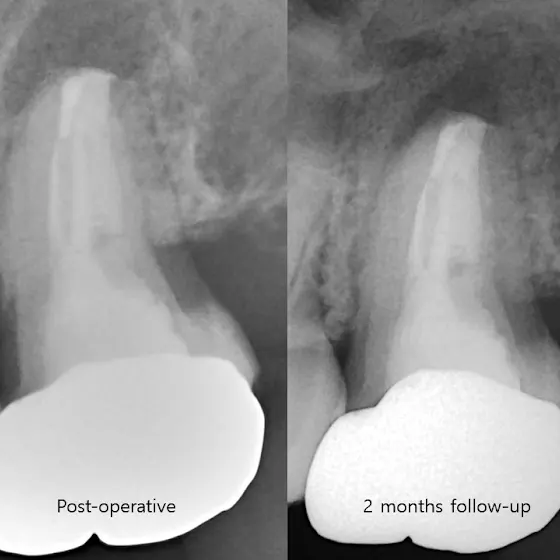

After Intentional Replantation,

A 2-month follow-up radiograph was obtained. The periapical radiolucency was decreased. The patient was satisfied with normal function.